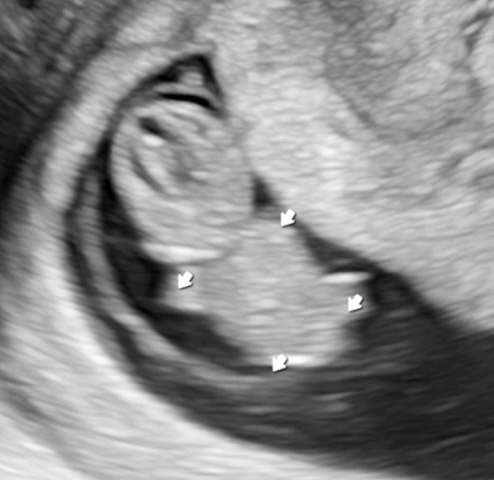

7주에 마지막으로 보고 2주동안 못봤는데 어제부터 입덧, 가슴통증이 사라져서 너무 걱정됐어요 계류유산 경험이 있는지라 ㅠ 회사 근처 병원에 갔더니 주수대로 잘 크고 심박수도 174까지 올라있더라구요 팔다리도 작게 뿅 생기고 잘 크고있다니까 눈물이 주륵 흐르는데ㅠㅠ 그리고 신기하게도 병원갔다오니까 입덧이 다시 시작 됐어요.....;; 같은 걱정이신 분들 계실 것 같아서 경험 공유합니다!